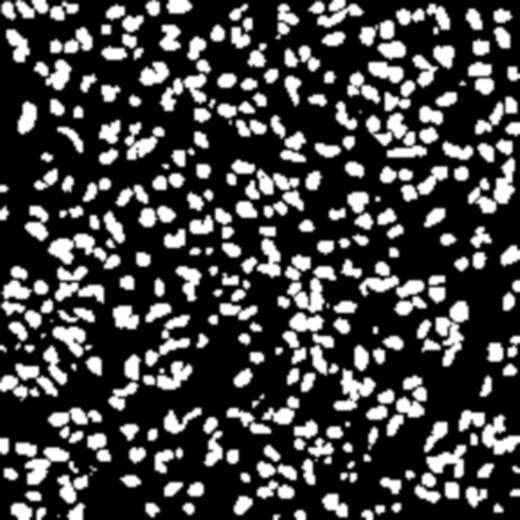

Most recent semantic segmentation methods adopt a U-Net framework with an encoder-decoder architecture. It is still challenging for U-Net with a simple skip connection scheme to model the global multi-scale context: 1) Not each skip connection setting is effective due to the issue of incompatible feature sets of encoder and decoder stage, even some skip connection negatively influence the segmentation performance; 2) The original U-Net is worse than the one without any skip connection on some datasets. Based on our findings, we propose a new segmentation framework, named UCTransNet (with a proposed CTrans module in U-Net), from the channel perspective with attention mechanism. Specifically, the CTrans module is an alternate of the U-Net skip connections, which consists of a sub-module to conduct the multi-scale Channel Cross fusion with Transformer (named CCT) and a sub-module Channel-wise Cross-Attention (named CCA) to guide the fused multi-scale channel-wise information to effectively connect to the decoder features for eliminating the ambiguity. Hence, the proposed connection consisting of the CCT and CCA is able to replace the original skip connection to solve the semantic gaps for an accurate automatic medical image segmentation. The experimental results suggest that our UCTransNet produces more precise segmentation performance and achieves consistent improvements over the state-of-the-art for semantic segmentation across different datasets and conventional architectures involving transformer or U-shaped framework. Code: https://github.com/McGregorWwww/UCTransNet.